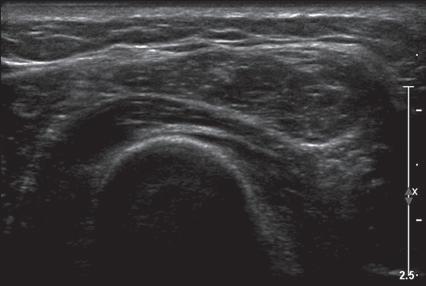

Musculoskeletal structures have characteristic appearances on ultrasound imaging.2 Normal tendons appear hyperechoic with a fiber-like or fibrillar echotexture (see Fig. 1.4).3 At close inspection, the linear fibrillar echoes within a tendon represent the endotendineum septa, which contain connective tissue, elastic fibers, nerve endings, blood, and lymph vessels.3 Continuous tendon fibers are best appreciated when they are imaged long axis to the tendon. On such a long axis image, by convention the proximal aspect is on the left side of the image, with the distal aspect on the right. In short axis, normal hyperechoic tendon fibers appear as bristles of a brush seen on end (see Fig. 1.9A). Normal muscle tissue appears relatively hypoechoic (Fig. 1.6). At closer inspection, the hypoechoic muscle tissue is separated by fine hyperechoic fibroadipose septa or perimysium, which surrounds the hypoechoic muscle bundles. The surface of bone or calcification is typically very hyperechoic, with posterior acoustic shadowing and possibly posterior reverberation if the surface of the bone is smooth and flat (Fig. 1.6). The hyaline cartilage covering the articular surface of bone is hypoechoic and uniform (Fig. 1.7A and B), whereas the fibrocartilage, such as the

labrum of the hip and shoulder, and the knee menisci are hyperechoic (Fig. 1.7B). Ligaments have a hyperechoic, striated appearance that is more compact compared with tendons (Fig. 1.8). In addition, ligaments are also identified in that they connect two osseous structures. Often normal ligaments may appear relatively hypoechoic when surrounded by hyperechoic subcutaneous fat; however, a compact linear hyperechoic ligament can be appreciated when imaged in long axis perpendicular to the ultrasound beam. Normal peripheral nerves have a fascicular appearance in which the individual nerve fascicles are hypoechoic, surrounded by hyperechoic connective tissue epineurium (Fig. 1.9).4 Hyperechoic fat is typically seen around larger peripheral nerves.

FIGURE 1.7 Cartilage. A, Ultrasound image transverse over the distal anterior femur shows hypoechoic hyaline cartilage (arrowheads) F, Femur. B, Ultrasound image of infraspinatus in long axis (I) shows a hyperechoic fibrocartilage glenoid labrum (arrowheads) and hypoechoic hyaline cartilage (curved arrow). Note hyperechoic epidermis and dermis (E/D), and adjacent deeper hypoechoic hypodermis with hyperechoic septa. G, Glenoid; H, humerus.